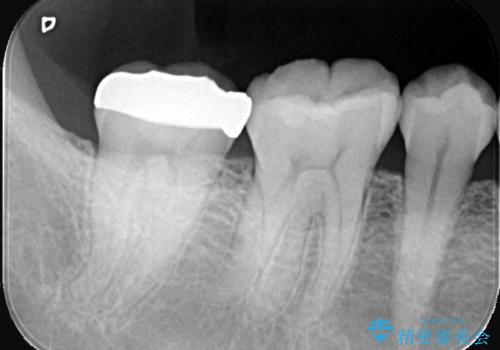

- 右下奥歯の詰め物が繰り返し欠けるとの主訴で来院されました。レントゲンとお口の中を詳細に診査した結果、以前の詰め物が咬み合わせの強い力に耐えきれず、また歯との適合も不十分であることが確認されました。患者様と相談し、今回は強度と耐久性に優れ、見た目も自然なセラミッククラウンで修復する治療計画を立案しました。これにより、再治療のリスクを減らし、長期的に安定した咬み合わせの回復を目指します。

治療では、まず古い詰め物を丁寧に取り除き、虫歯がないか確認しながら歯を丁寧に形を整えました。その後、精密な型取りを行い、患者様の歯の色や形に合わせたオーダーメイドのセラミッククラウンを作製しました。セラミックは天然歯のような透明感があり、非常に審美性に優れています。また、金属を使用しないため、金属アレルギーの心配もありません。